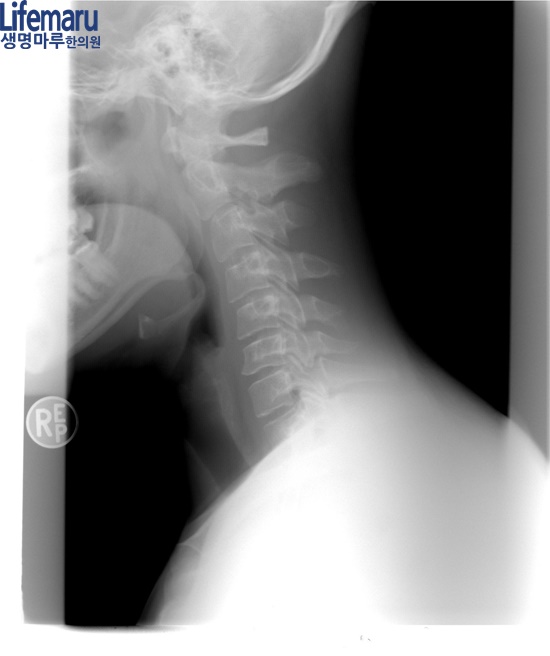

본원에서는 이러한 척추관절 통증 및

디스크 질환 등에 추나요법을 진행하고 있습니다.

추나요법은 한의사가 직접 손으로

밀고 당기며 치료하는 방식인데요.

주로 틀어짐을 교정하거나 통증을 완화하는 데

도움이 되는 치료입니다.